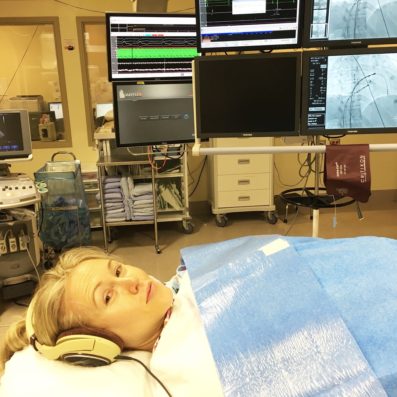

My birth experience is what finally gave me the courage to do the heart ablation surgery. It’s now August 2018, and it’s been a week since the surgery. Waiting in anticipation for this heart surgery – a procedure where I’d have to be awake, and one that could leave me with a pacemaker at 36 years old – was the scariest thing I’ve ever experienced.

But I did the surgery despite the raging fear. And it’s over. And I’m ok. Here’s what I learned.